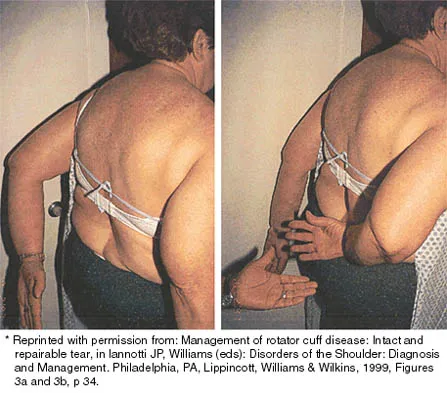

A 25-year-old man injured his dominant shoulder after falling on his outstretched arm 4 months ago. Examination reveals that he cannot lift his arm above 90 degrees, and he has pronounced medial scapular winging. Management should consist of

Explanation